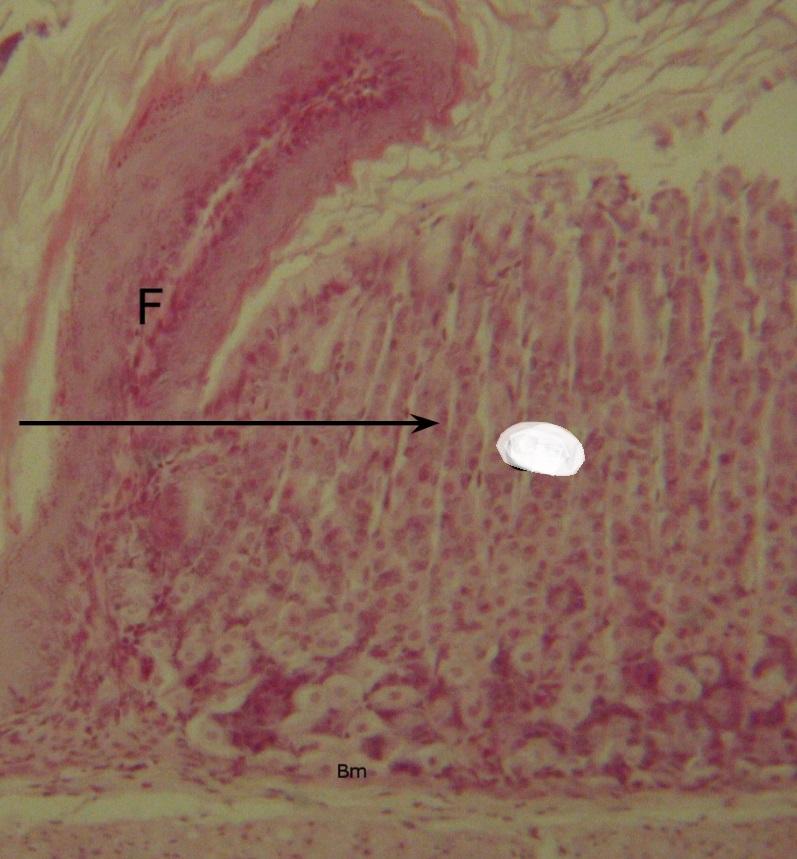

Pytanie 384

fałd błony śluzowej (przejście przełyku w żołądek)

Pytanie 385

gruczoły wpustowe (przejście przełyku w żołądek)